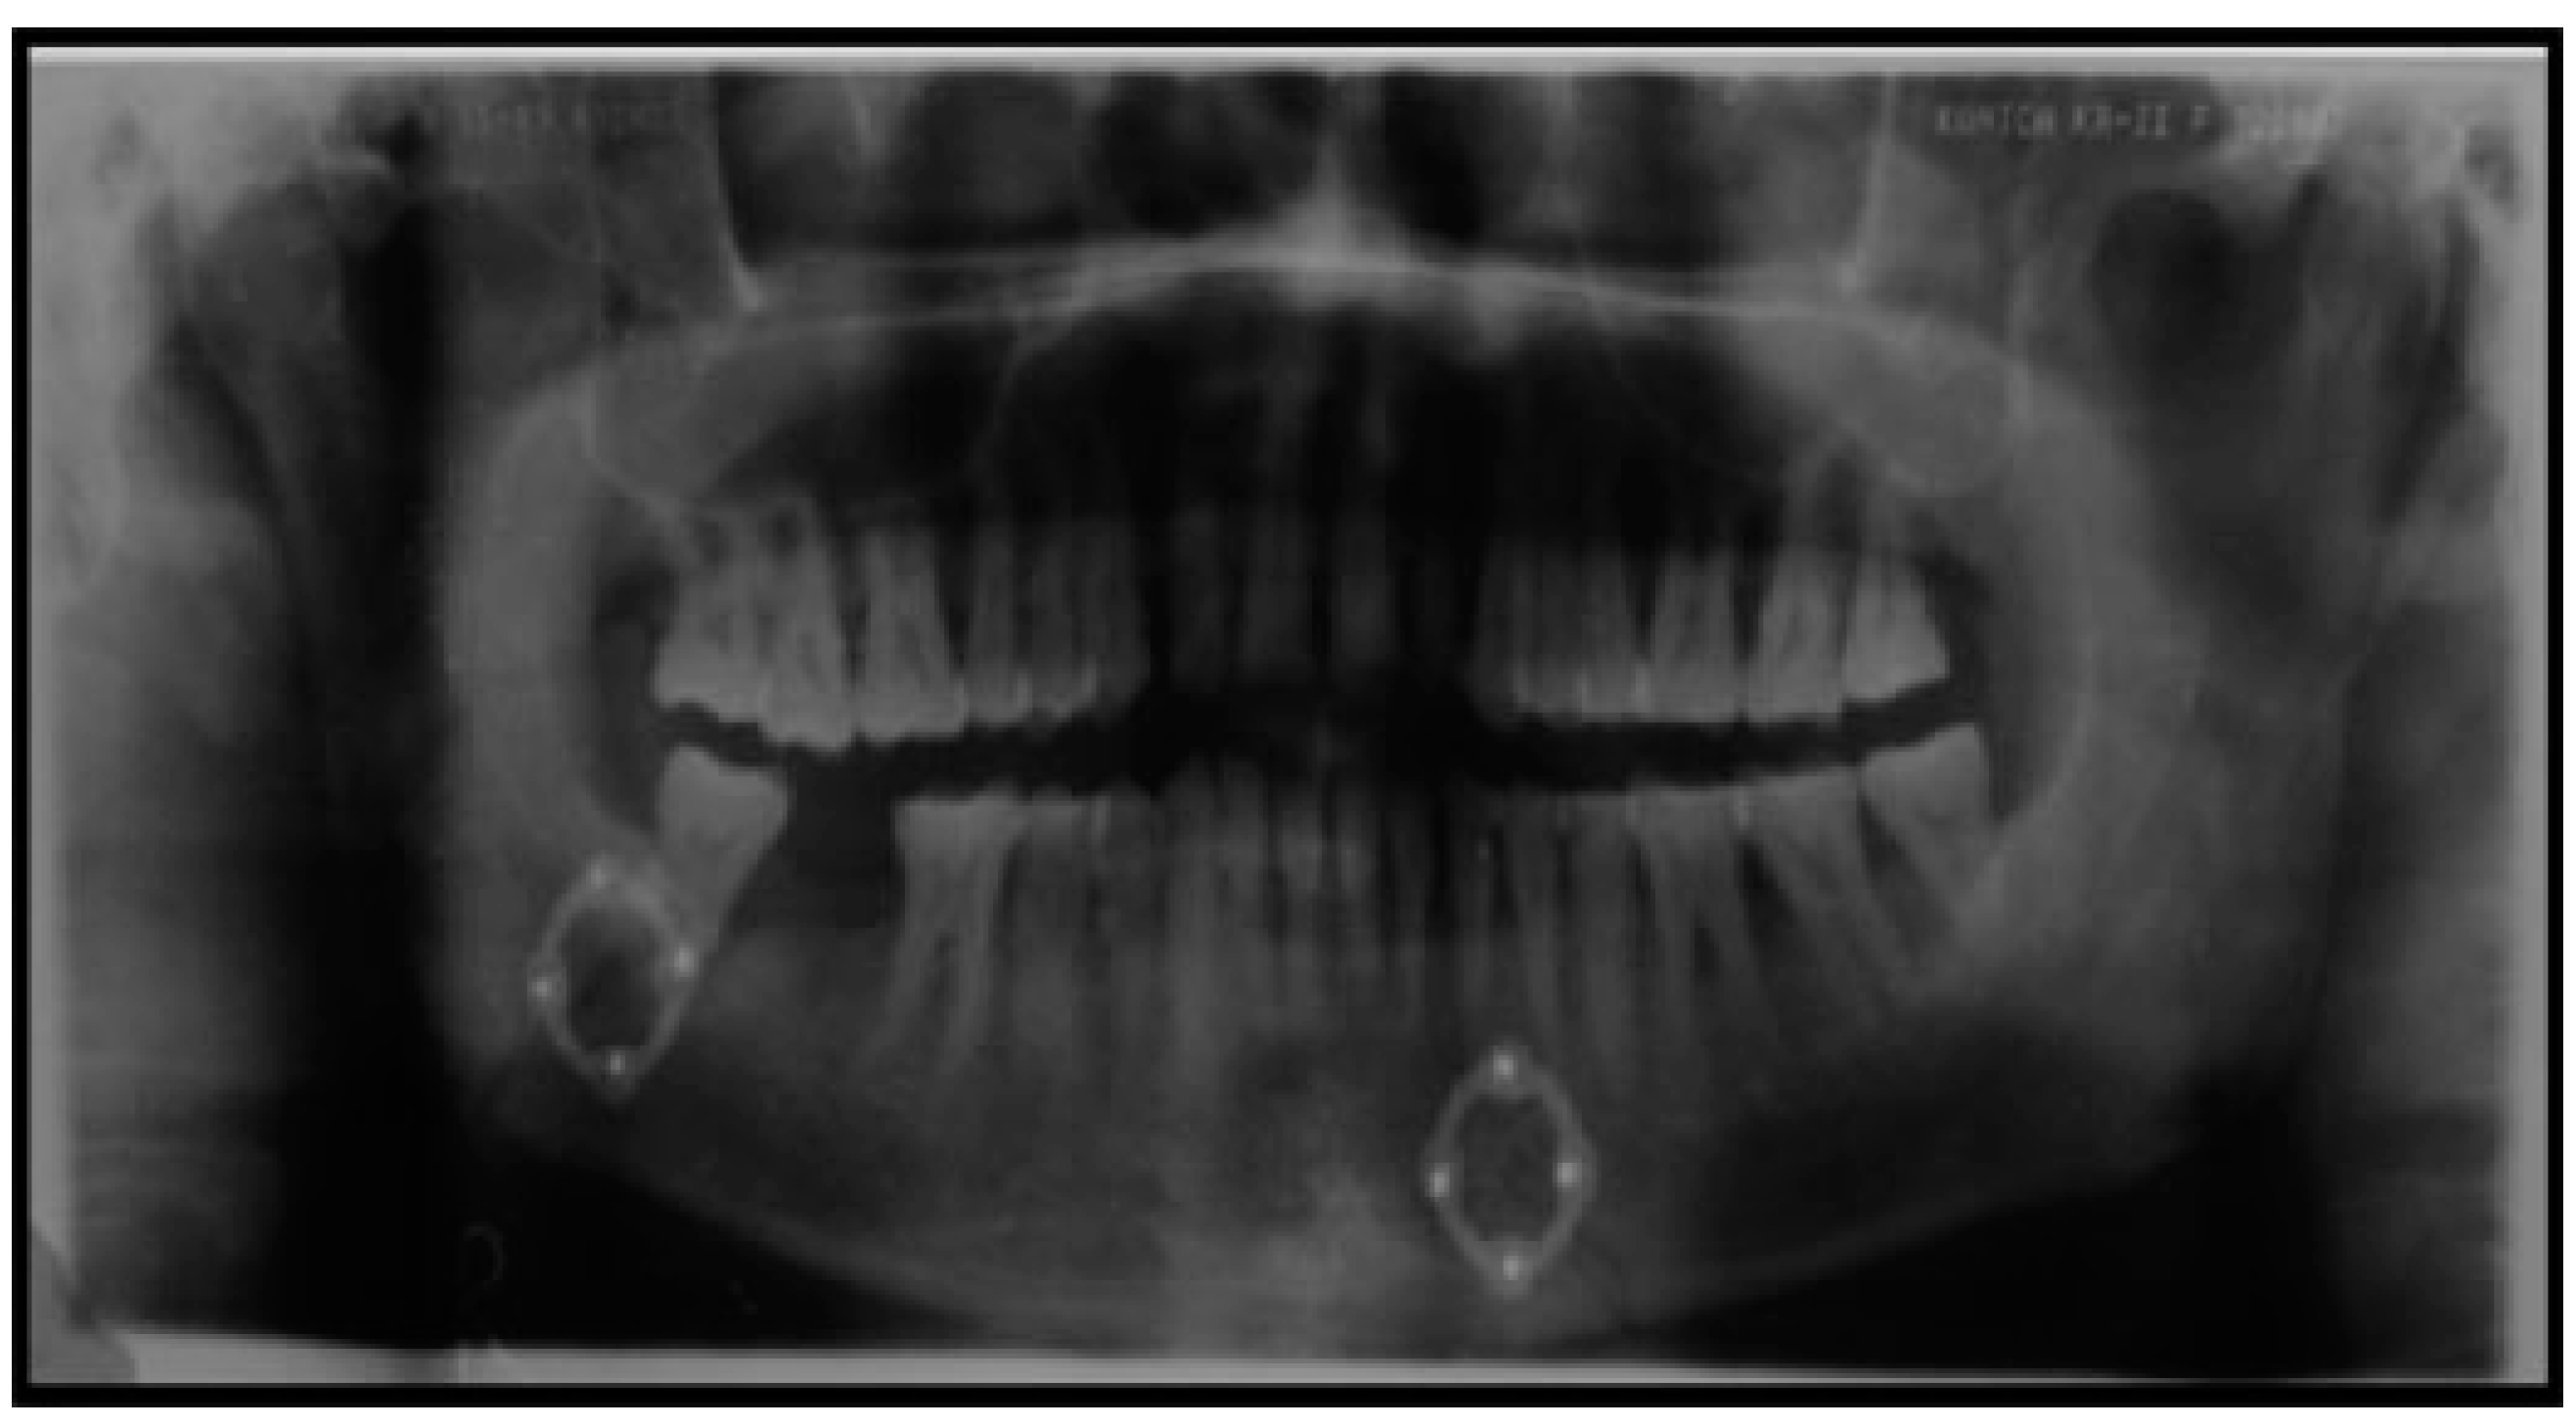

All the patients were treated by ORIF with the application of transient intermaxillary fixation using embrasure wiring [9] as intraoperative means of stabilizing occlusion along with 2.0 mm × 8.0 mm screws with 26-gauge stainless steel wire placed across the fracture line in mandibular angle to stabilize the fracture. Fixation of fracture was achieved using single 3D titanium locking miniplate placed with the help of transbuccal trocar or Synthes 90-degree hand piece and screw driver. The method of using transbuccal trocar or Synthes 90 degrees is totally dependenton thepersonal discretion of the surgeon. 3D locking titanium miniplates used in our study was four-holed, box-shaped plate, and screws with 2 mm diameter and 8 mm length. ORIF for all patients was done under general anesthesia with nasoendotracheal intubation (Figure 1 and Figure 2). Prior to the application of the 3D locking miniplates in the patients;, a prefabricated stereolithographic simulation replica model was made with the help of polymethyl methacrylate (PMMA) to help in contouring of the plate. Hence, simulation of the surgery was done beforehand to ensure the maximum adaptability of plate across the fracture line.

Figure 1. Right mandibular angle fracture with left parasymphysis fracture.